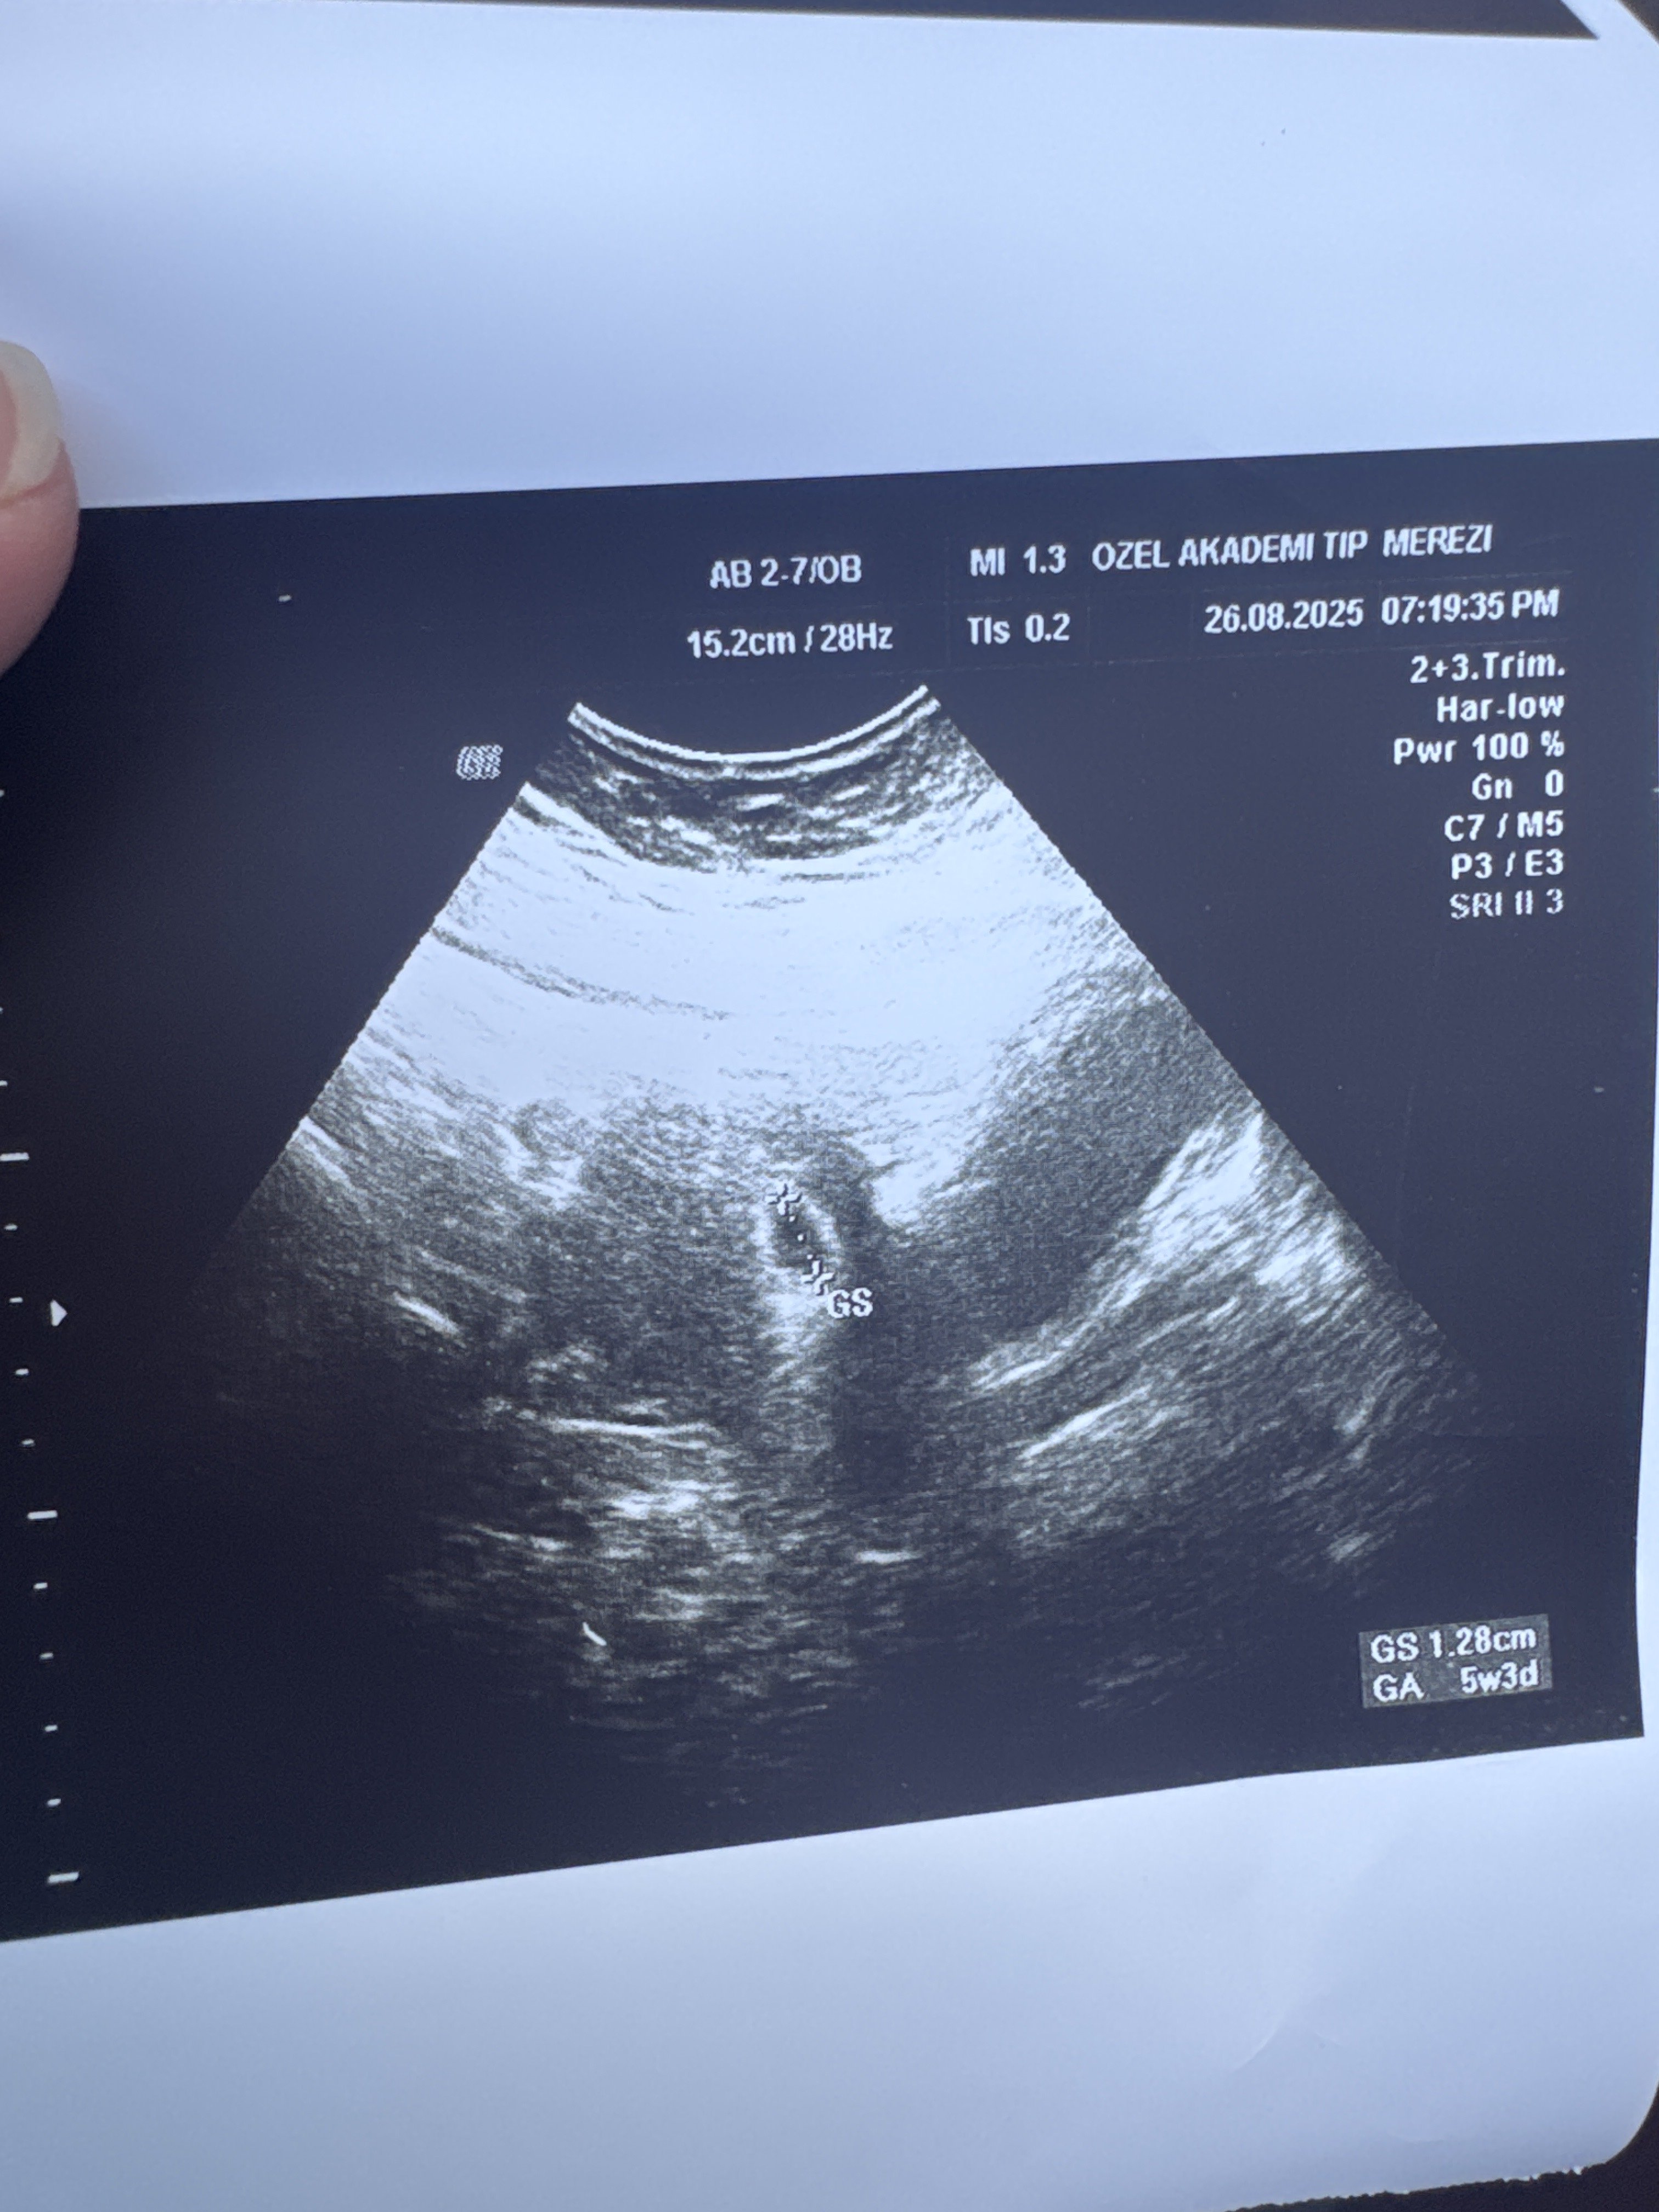

Arkadaşlar merhaba ilk bebeğim olacak inşallah. Dün ilk kez doktora gözüktüm ilk göbekten sonra vajinal baktı ikisinde de kese var ama bebek yok haftaya tekrar geldi dedi . İçim hiç rahat değil başına benzer bir durum gelen var mı yardım lütfen :(( kese görüntüsünü ekledim

Kızlar merhaba bende aynı durumdayım ben hamile olduğumu öğrendiğimde da beta 87 çıkmıştı daha sonra benim kanamam oldu hastaneye gittiğimde düşük tehlikesi de olabilir yerleşme kanaması da olabilir demişti o gün beta 2104 çıkmıştı ve kese yeni görünmeye başlıyordu iki gün önce gittim 5+3 gündü son adet tarihine göre 13mm kese yi ölçtü kese var benek yok yolk saç da yok hatta 5 gün önce 6 mm ölçmüşlerdi kese de büyüme de var ama benek yok dedi bi bu haftalarda yolk saç görmeyi bekleriz ama göremedim dedi beta istedi sonuç 19500 çıktı iki gün sonra gel demişti çalıştığım için bugün gidemedim haftaya cuma ya gideyim diye düşündüm o gün 6+6 olacak herhalde o gün belli olur çok korkuyorum boş gebelik demesinden bi önceki hamileliğimde sağlıksız gebelik olmuştu çünkü 6. Haftada kalmıştı bebek kürtaj olmak zorunda kalmıştım aynı şeyi yaşamaktan çok korkuyorum dua edin lütfen 🙏🏻